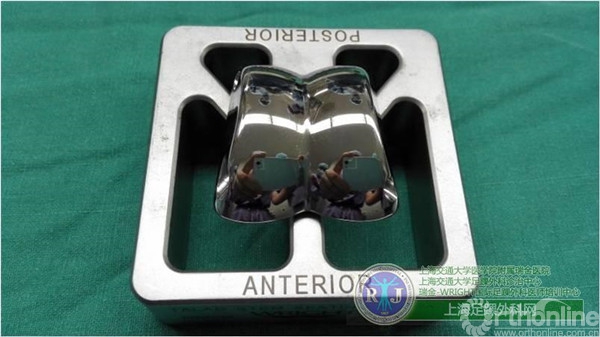

为了改变这种现状,造福广大的踝关节炎患者,瑞金医院足踝外科率先在国内开展第三代全踝关节假体置换手术,使用美国Wright公司的第三代全踝人工关节系统——INBONE II为这名患者解决病痛。

上海瑞金医院骨科足踝外科团队于2015年10月28日上午成功对该患者实施了第三代全踝关节假体(INBONE® II. Wright.)置换手术,手术过程非常顺利。手术中首先清理踝关节内外侧炎性组织及骨赘,将患足置于专门的定制支架中,在透视下反复调整足踝及导针位置,力求最高精确度。在截骨导板的定位下进行踝关节胫骨及距骨的截骨,试样假体大小,置入合适匹配的踝关节假体及垫片完成全踝关节假体的置换,全程手术时间90分钟。完成的全踝关节假体置换位置精确,假体设计稳定牢固,踝关节内外侧软组织平衡,达到了预期的效果。术后患者恢复良好,手术取得圆满成功。患者在休养五周左右以后可以下地行走,去除踝关节炎疼痛畸形的同时能够保留踝关节的活动度,为生活和工作提供极大便利。